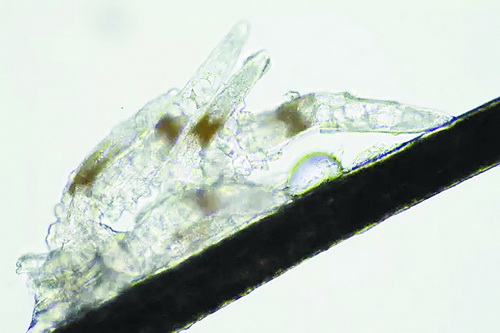

顯微鏡下長(zhǎng)在睫毛中的螨蟲(chóng)

冬天來(lái)了,氣溫降低,睫毛上的“隱形殺手”蠕形螨卻沒(méi)有要冬眠的意思。廈門(mén)大學(xué)附屬?gòu)B門(mén)眼科中心11月初開(kāi)設(shè)蠕蟲(chóng)性瞼緣炎門(mén)診以來(lái),每天來(lái)查螨的市民都特別多,短短一個(gè)多月,已有近千人在顯微鏡下見(jiàn)到長(zhǎng)期寄居在自己睫毛上,朝夕相處,卻素未謀面的蠕形螨。

蠕形螨怎么就跑進(jìn)眼睛里了呢?原來(lái),蠕形螨以吃角質(zhì)蛋白、油脂為生,而我們的睫毛和瞼板腺等地方油脂分泌旺盛,正是螨蟲(chóng)寄居的理想場(chǎng)所。蠕形螨有兩種,一種是寄生在睫毛、眉毛毛囊里的毛囊蠕形螨,一種是寄生在皮脂腺和瞼板腺內(nèi)的皮脂蠕形螨,它們?cè)谘劬镂秤椭?、吞噬上皮?xì)胞、產(chǎn)卵、排泄,會(huì)引發(fā)一系列不良反應(yīng)。